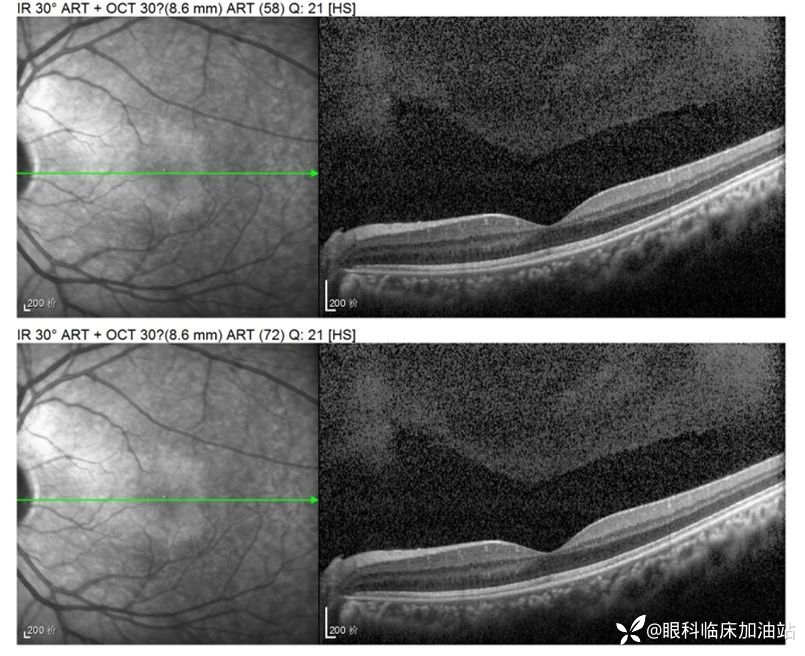

OCT